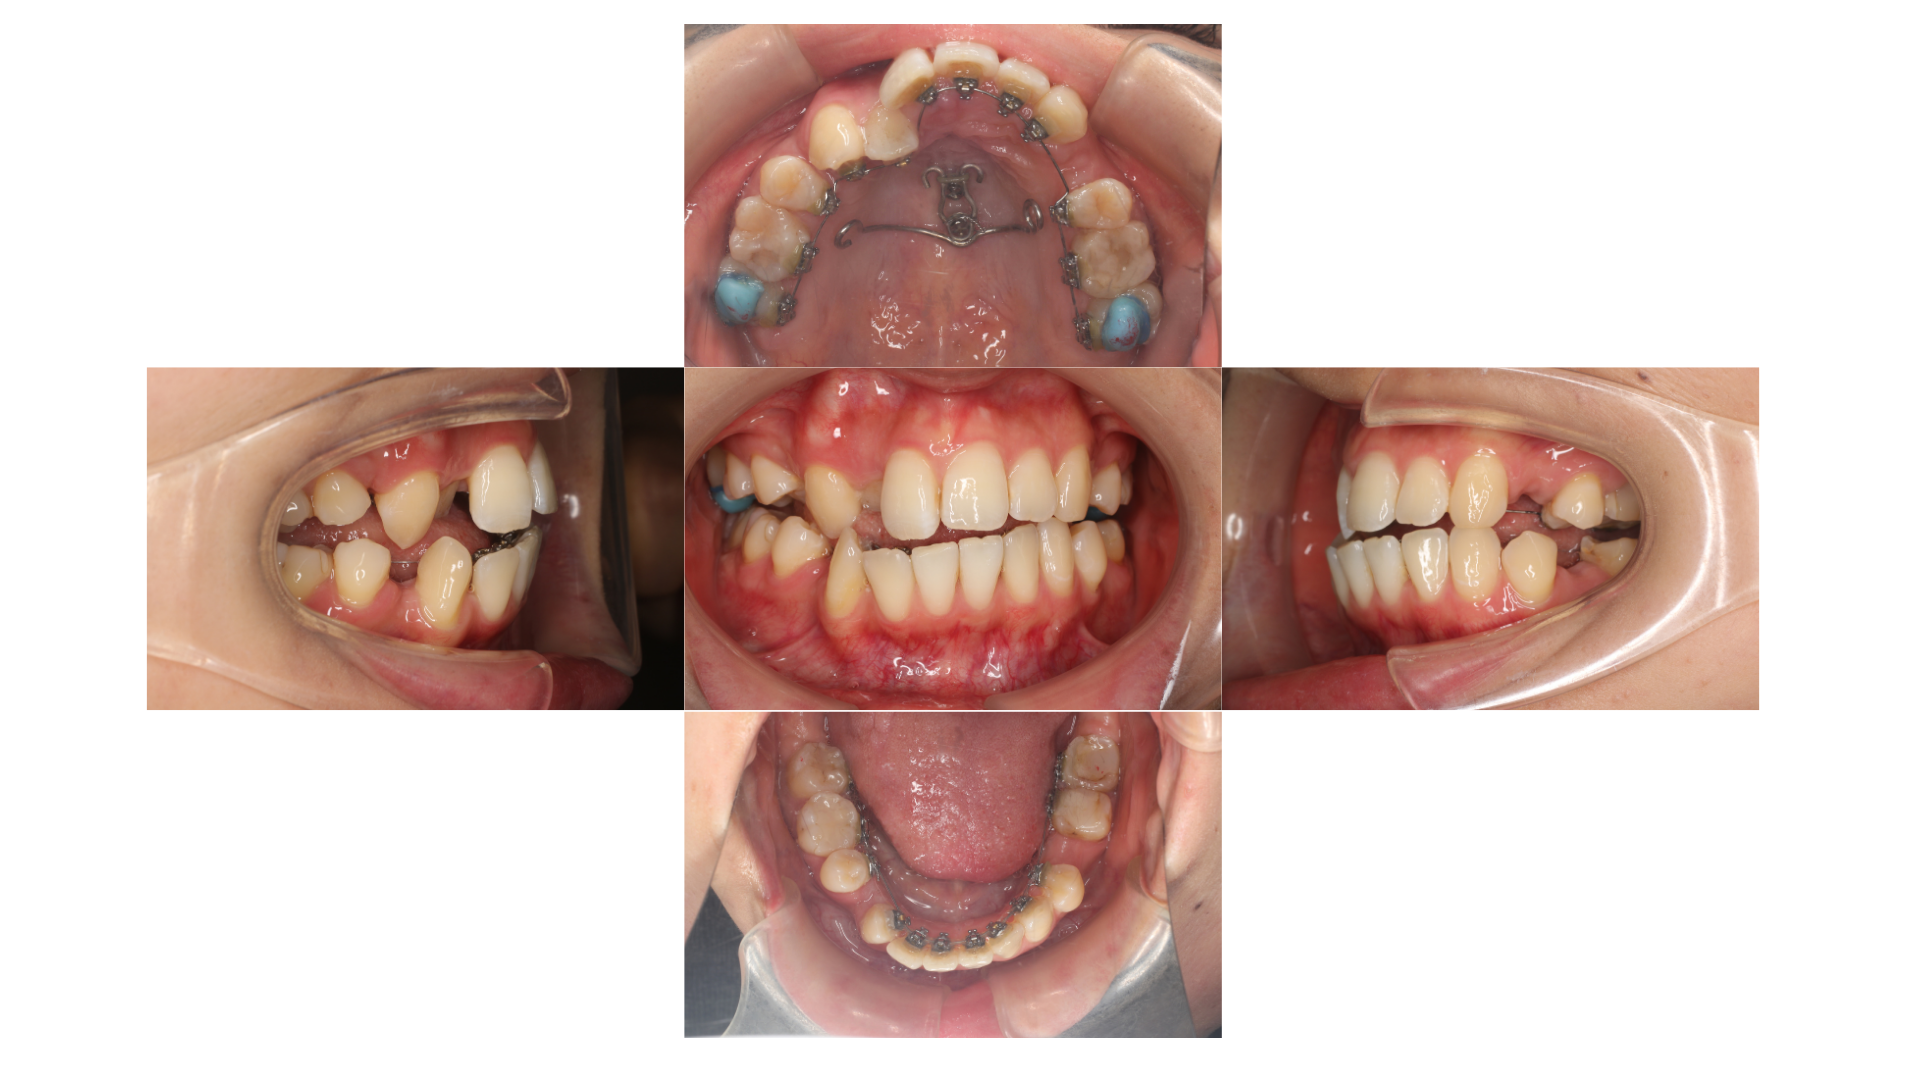

初診時